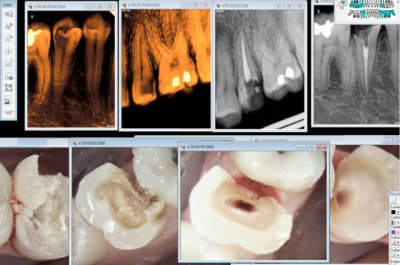

bon ba voilà les copains ! j'ai commencé ma séance CFAO vers 10h30 ce matin. Scanner , modéliser , 16 couronnes !! maintenant je vais pouvoir enfin grignoter un morceau ..

Sur ces 16 couronnes , 6 sont des "na rentre pas , faut refaire" fuck putty ! avec un mix de bridge full zr, chappe zr avec ceramique strate et ZR eco ! donc du zouli et du moche :)

Si ça peu vous donner une idée du temps qu'il faut :) pour les futurs geek :)

Ca marche en 2D aussi. Là il faut faire 2 couronnes. -)

Ah ! oui je vois. -)